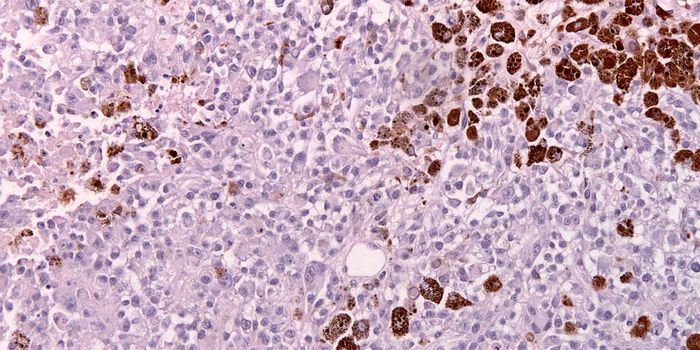

NOV 22, 2023ImmunologyA characteristic of tumors includes the ability to avoid the immune system. In many cases tumors can progress without de ...